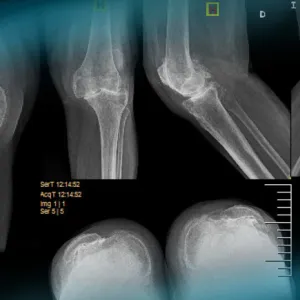

A 48-year-old female professional rower sustained a right knee injury in a motor accident, presenting with pain, swelling, and a range of motion (ROM) limited to 0–90 degrees. Physical examination revealed a positive Lachman test.